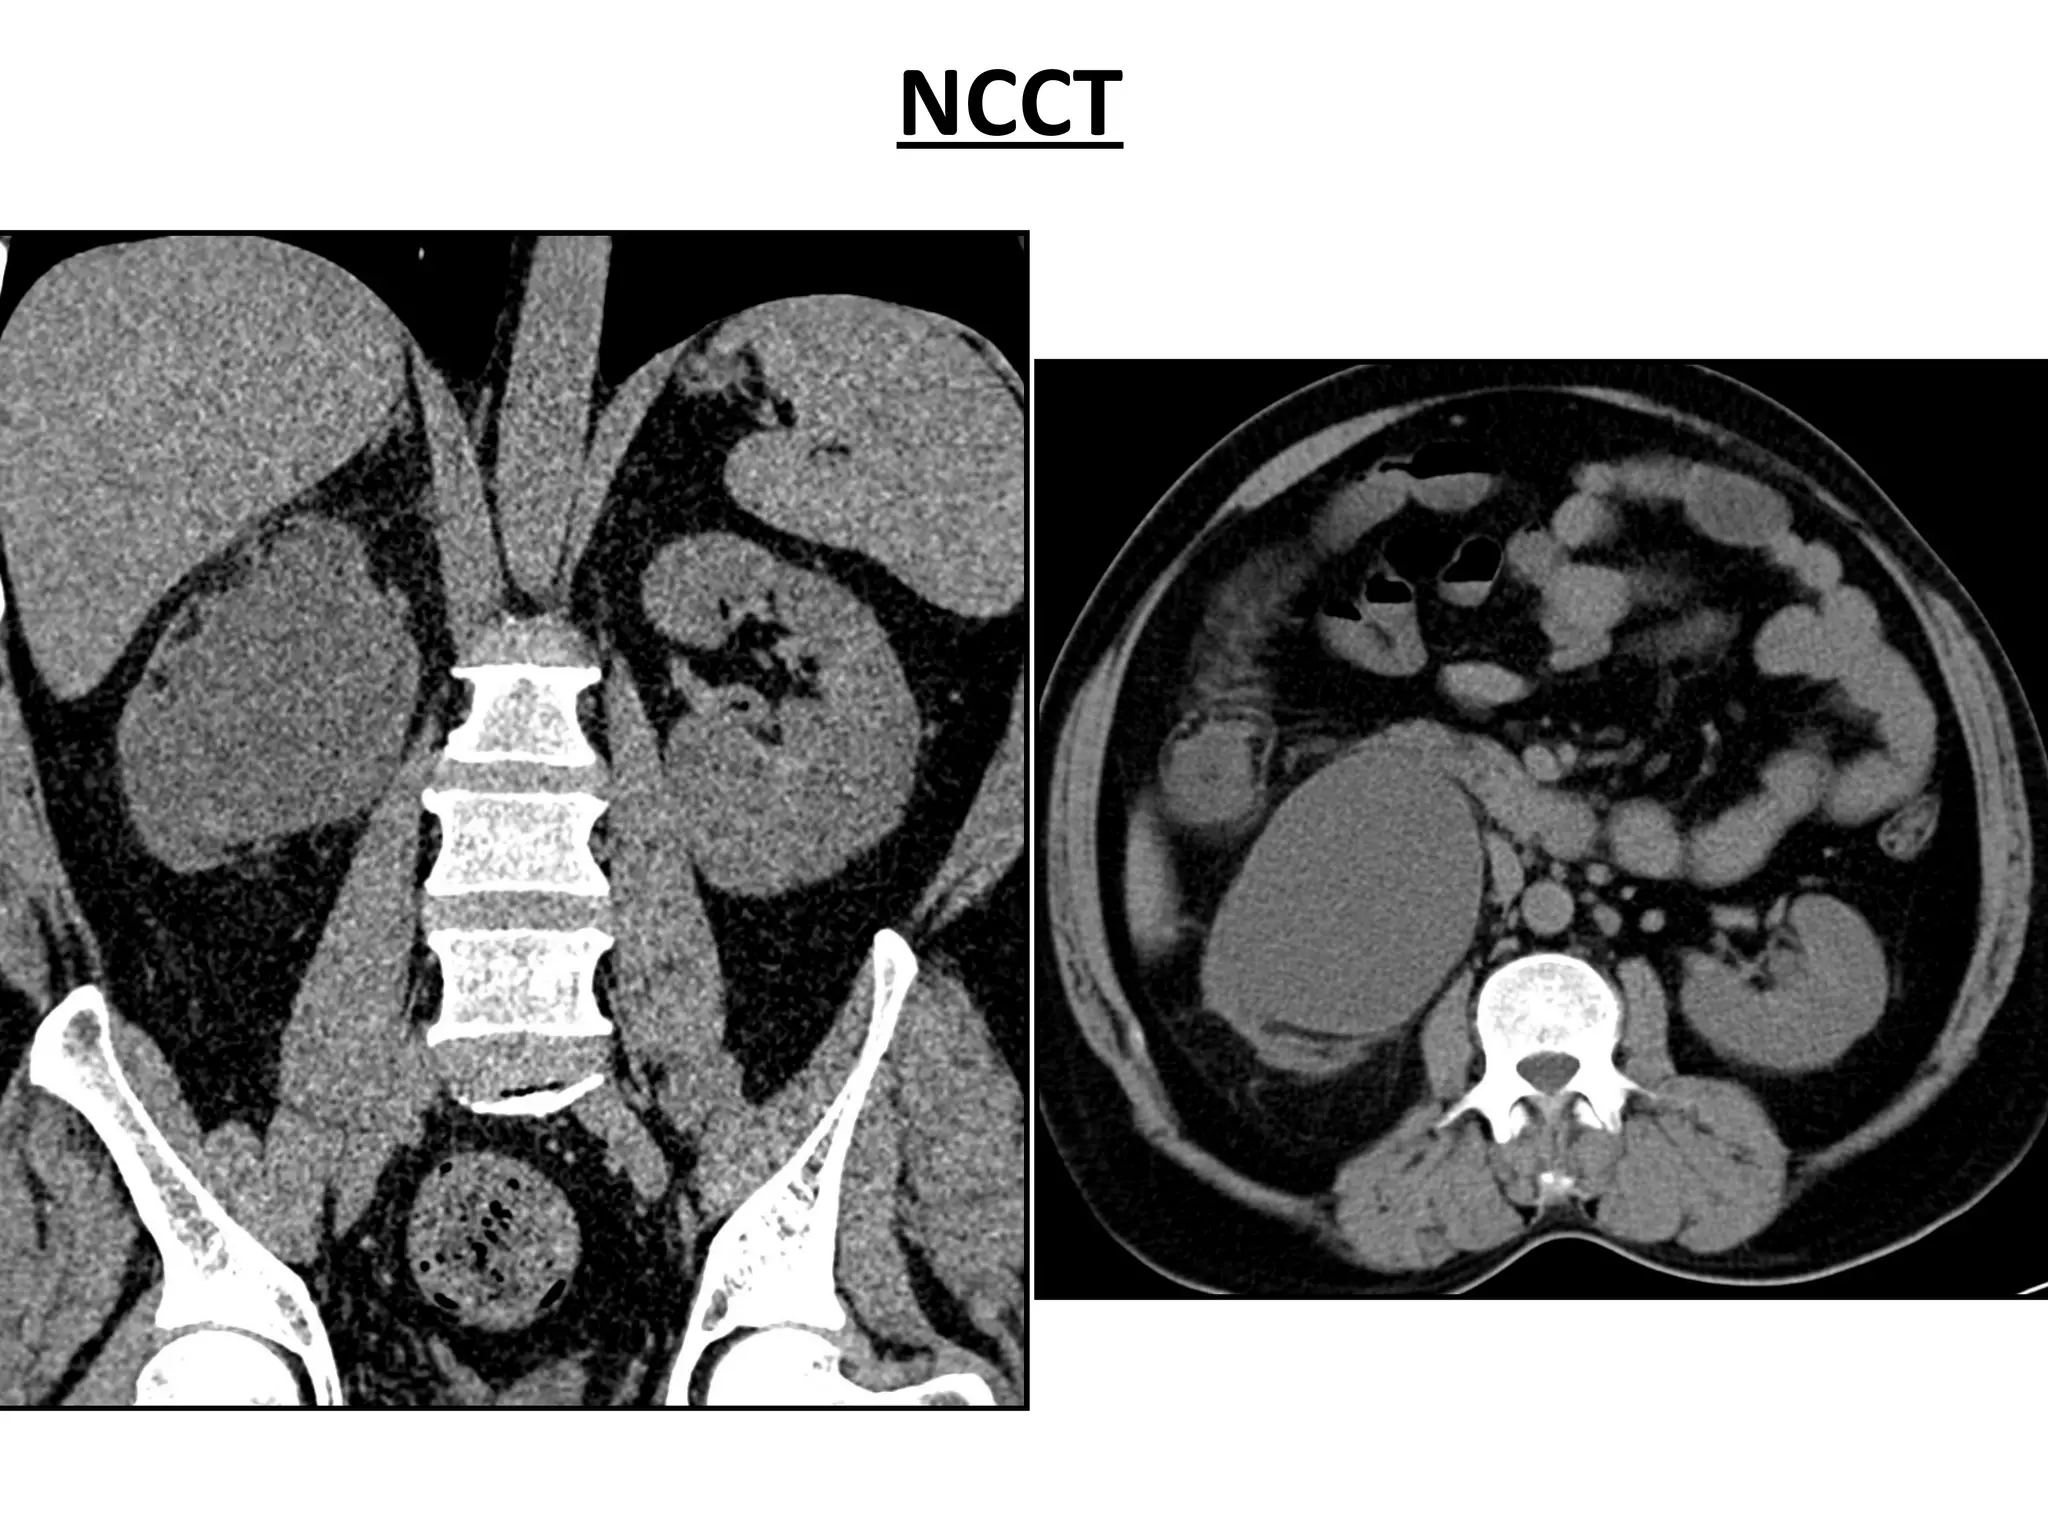

NCCT

Index case • 45/M •C/C - On/ off Right flank pain x 3 mnths - H/O High grade fever before 1 mnth • Past H/O - No medical / surgical illness • Pers. H/O - Chronic alcoholic & smoker • O/E - Obese with BMI – 30.5 kg/m² • Vitals - Tº - Afebrile , P- 78/min , B.P.- 130/80 mmhg • P/A - Soft , Non-tender • Blood Investigations & Urine C/S - Normal • USG - Rt. Grossly hydronephrotic kidney with thinned out parenchyma - Lt kidney normal in position, shape & size • IVP - Non visualization of the right kidney - Left kidney normal excretion & function • DTPA -NON VISUALIZED right kidney, left kidney GFR 55ml/min